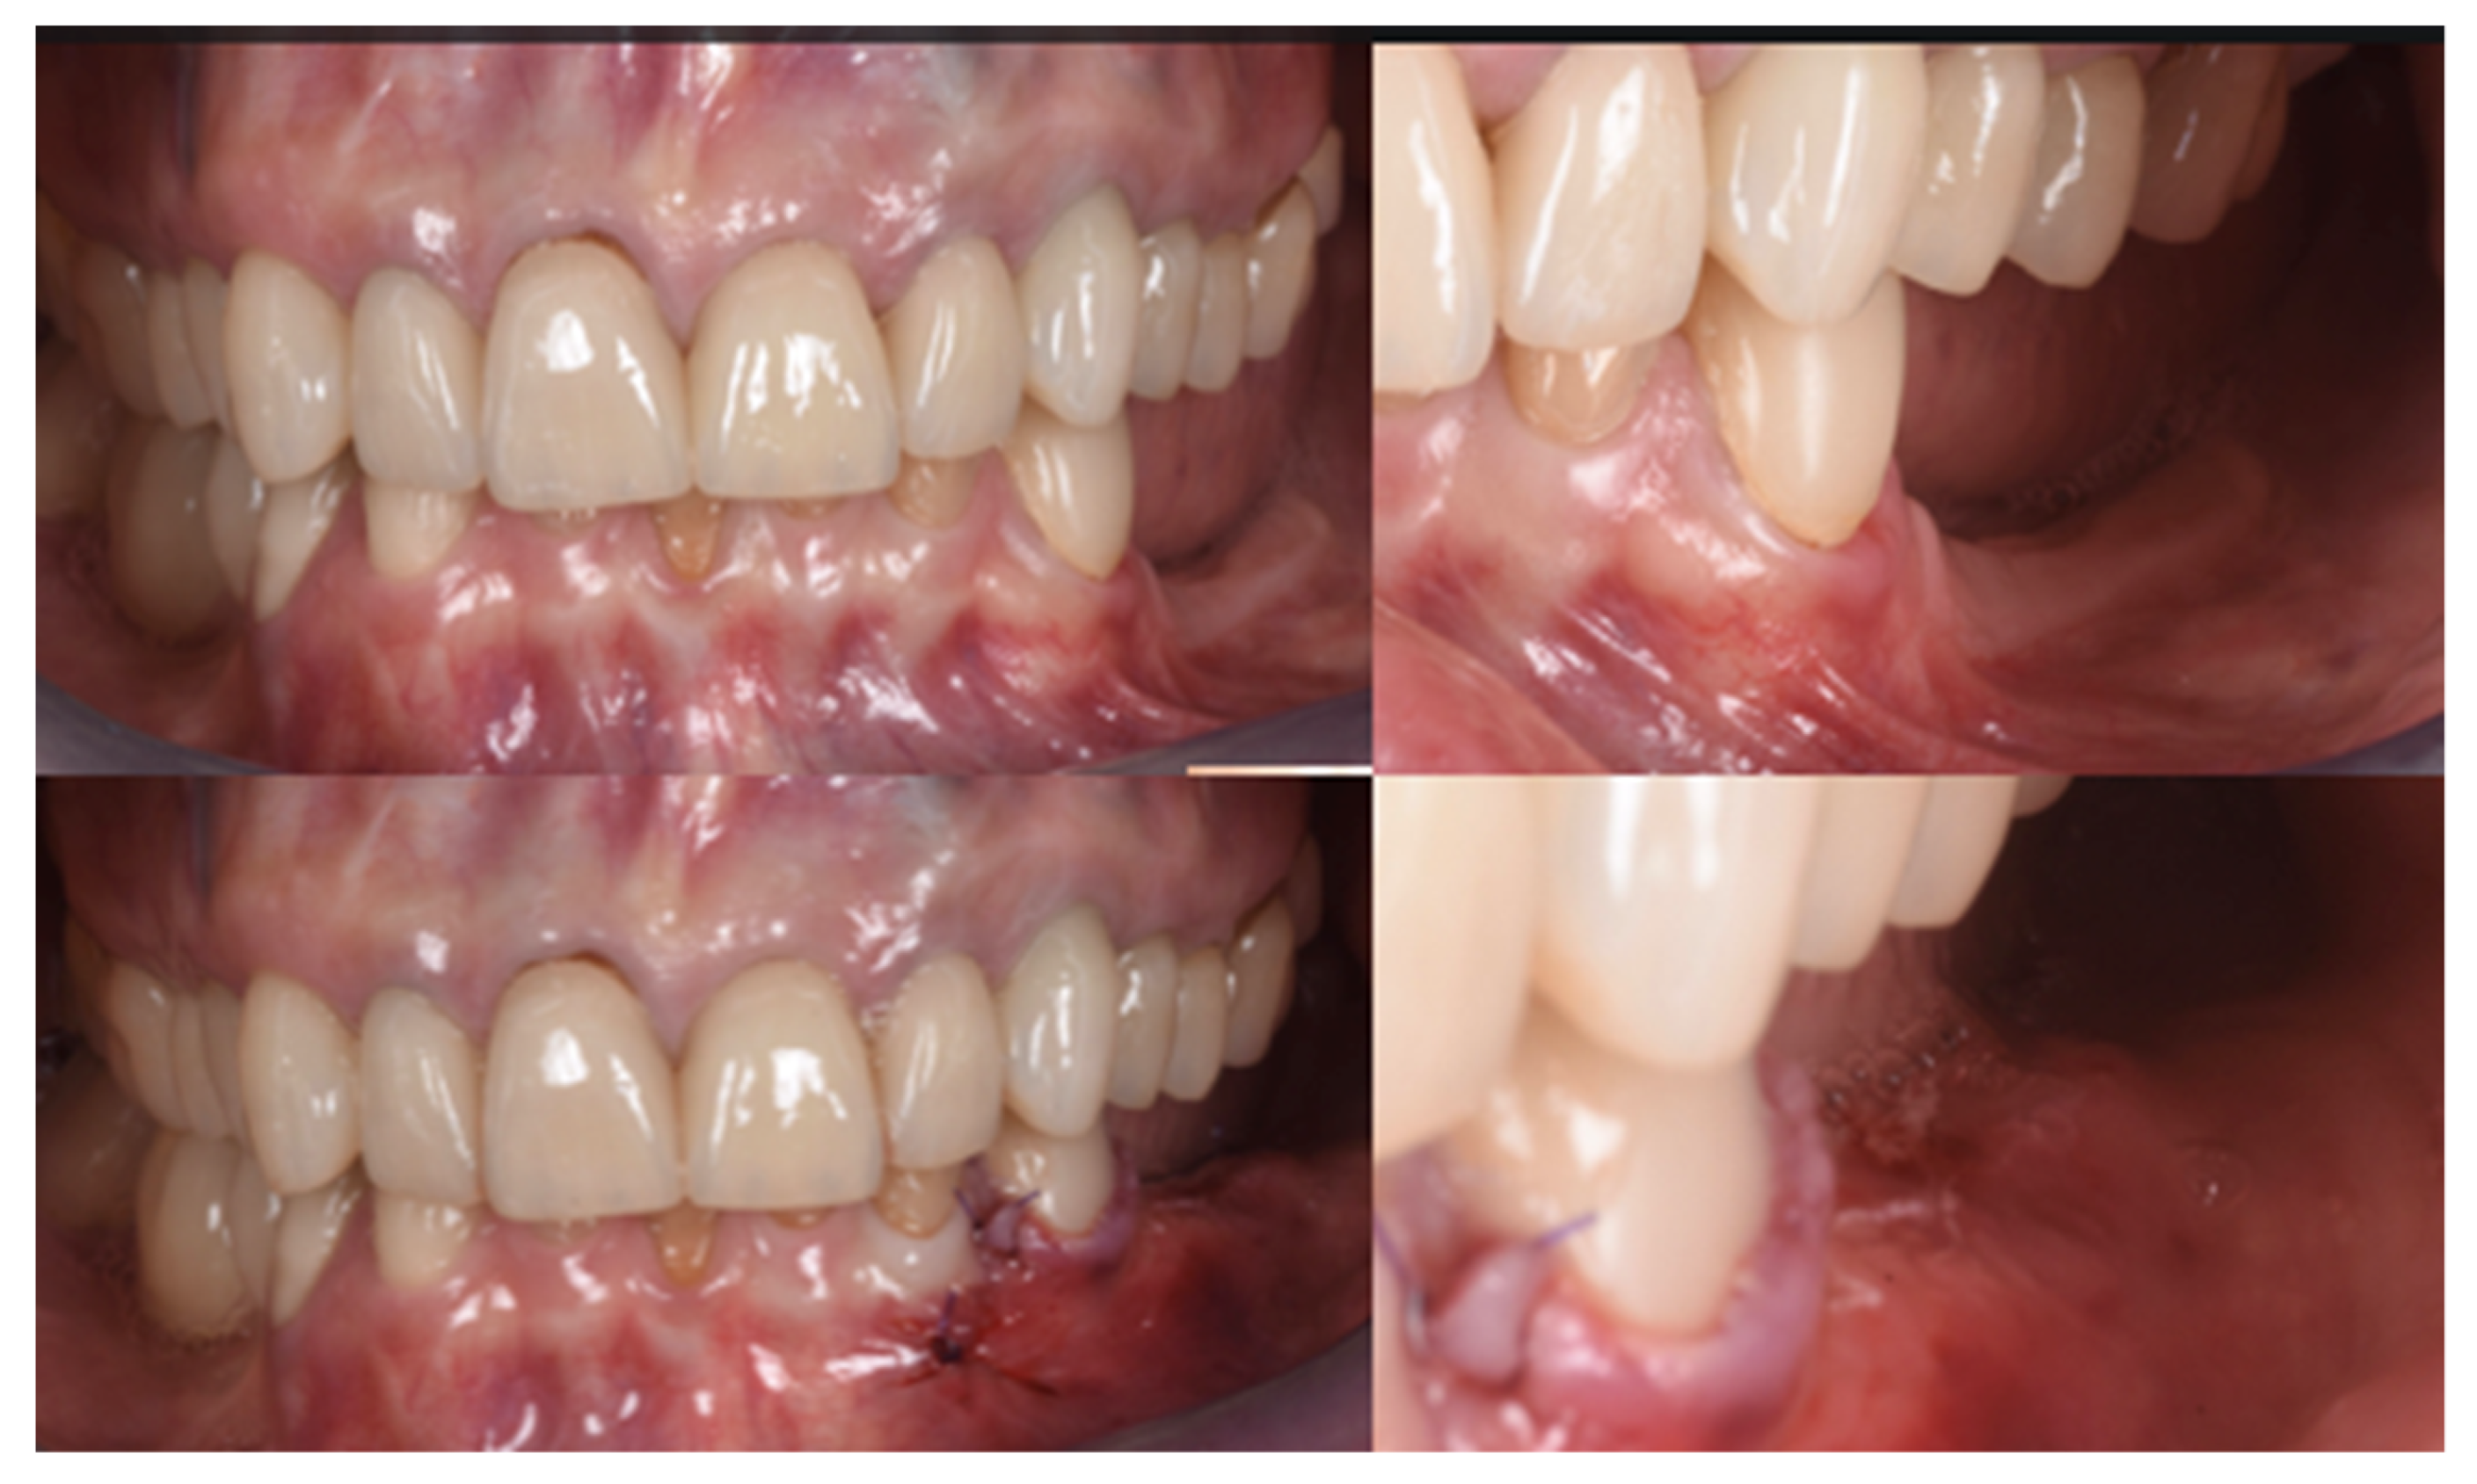

Figure 10.

Clinical evaluation after 18 months of prosthetic loading.

Two implants (Institute Straumann, Basel, Switzerland) of 4 × 12 mm and 5 × 8 mm were inserted in the 3.4 and 3.6 areas, respectively (Figure 9a). The final prosthesis was manufactured with a digital workflow and delivered after three months. The patient was monitored with clinical and radiographic evaluations 12 and 18 months after prosthetic loading. The clinical examination and the digital scans at 12 months of follow-up proved the efficacy of the regenerative approach (Figure 10 and Figure 11). The comparison between 12 (Figure 9b) and 18 month (Figure 9c) radiographs showed stability of the bone crest around the dental implants. Furthermore, a progressive mineralization of the regenerated area was also evident (Figure 9a–c).